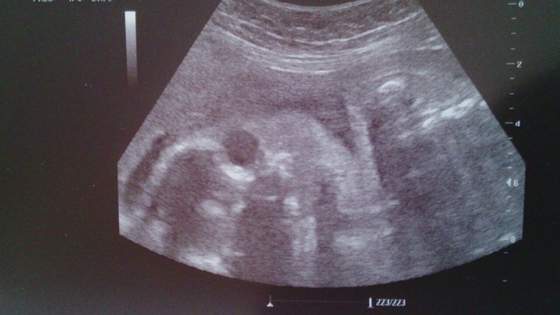

DSC_0005.jpgOto buźka mojej Amelki